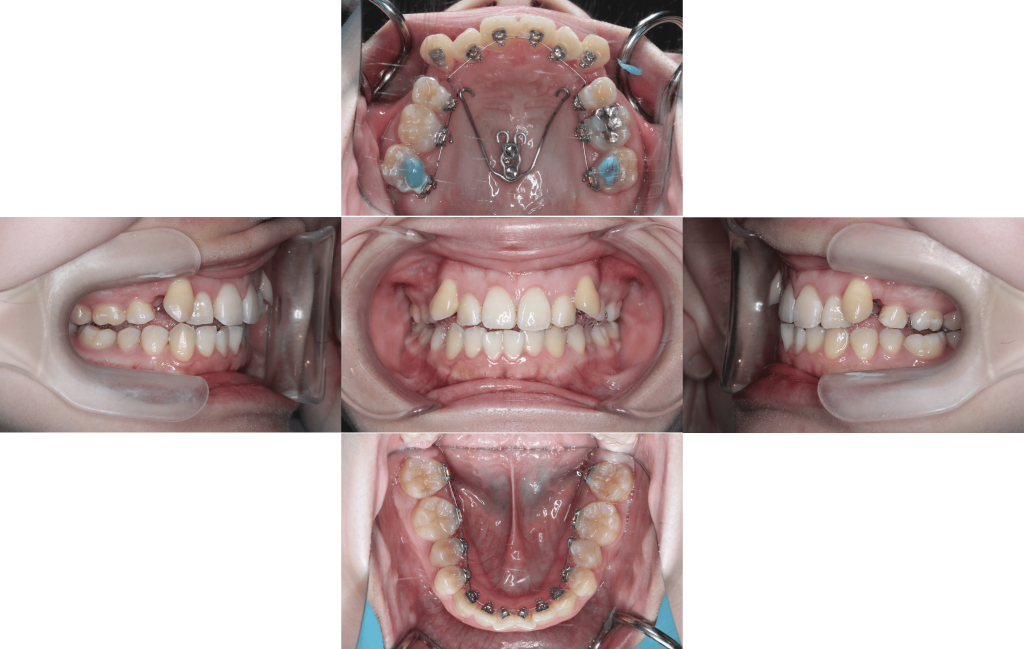

初診

装置装着